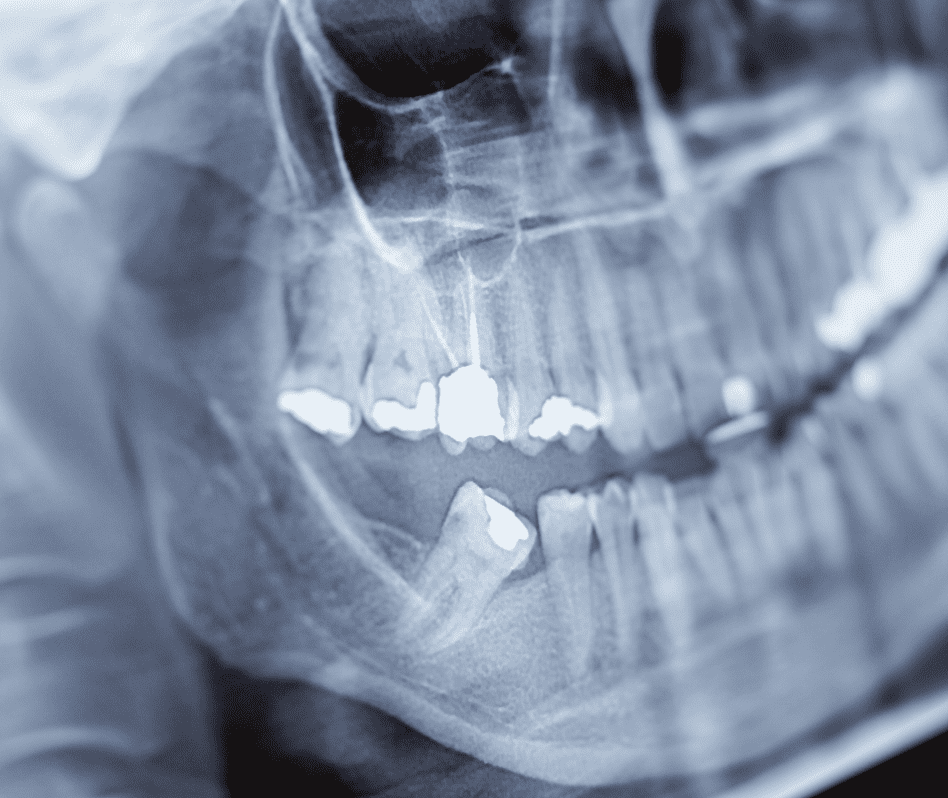

La regeneración ósea dental en Paterna es un procedimiento avanzado que permite recuperar el volumen y la calidad del hueso maxilar cuando se ha perdido debido a infecciones, enfermedad periodontal, traumatismos o ausencia prolongada de dientes.

La regeneración ósea dental es un procedimiento quirúrgico que estimula la formación de hueso nuevo en zonas donde se ha perdido. Se utilizan biomateriales biocompatibles y técnicas específicas que favorecen la regeneración natural del organismo.

Este tratamiento es fundamental cuando no existe suficiente hueso para colocar implantes dentales o cuando se ha producido una reabsorción ósea importante.

Como especialista en regeneración de hueso dental, evaluamos cada caso mediante diagnóstico clínico y radiológico para determinar la técnica más adecuada.